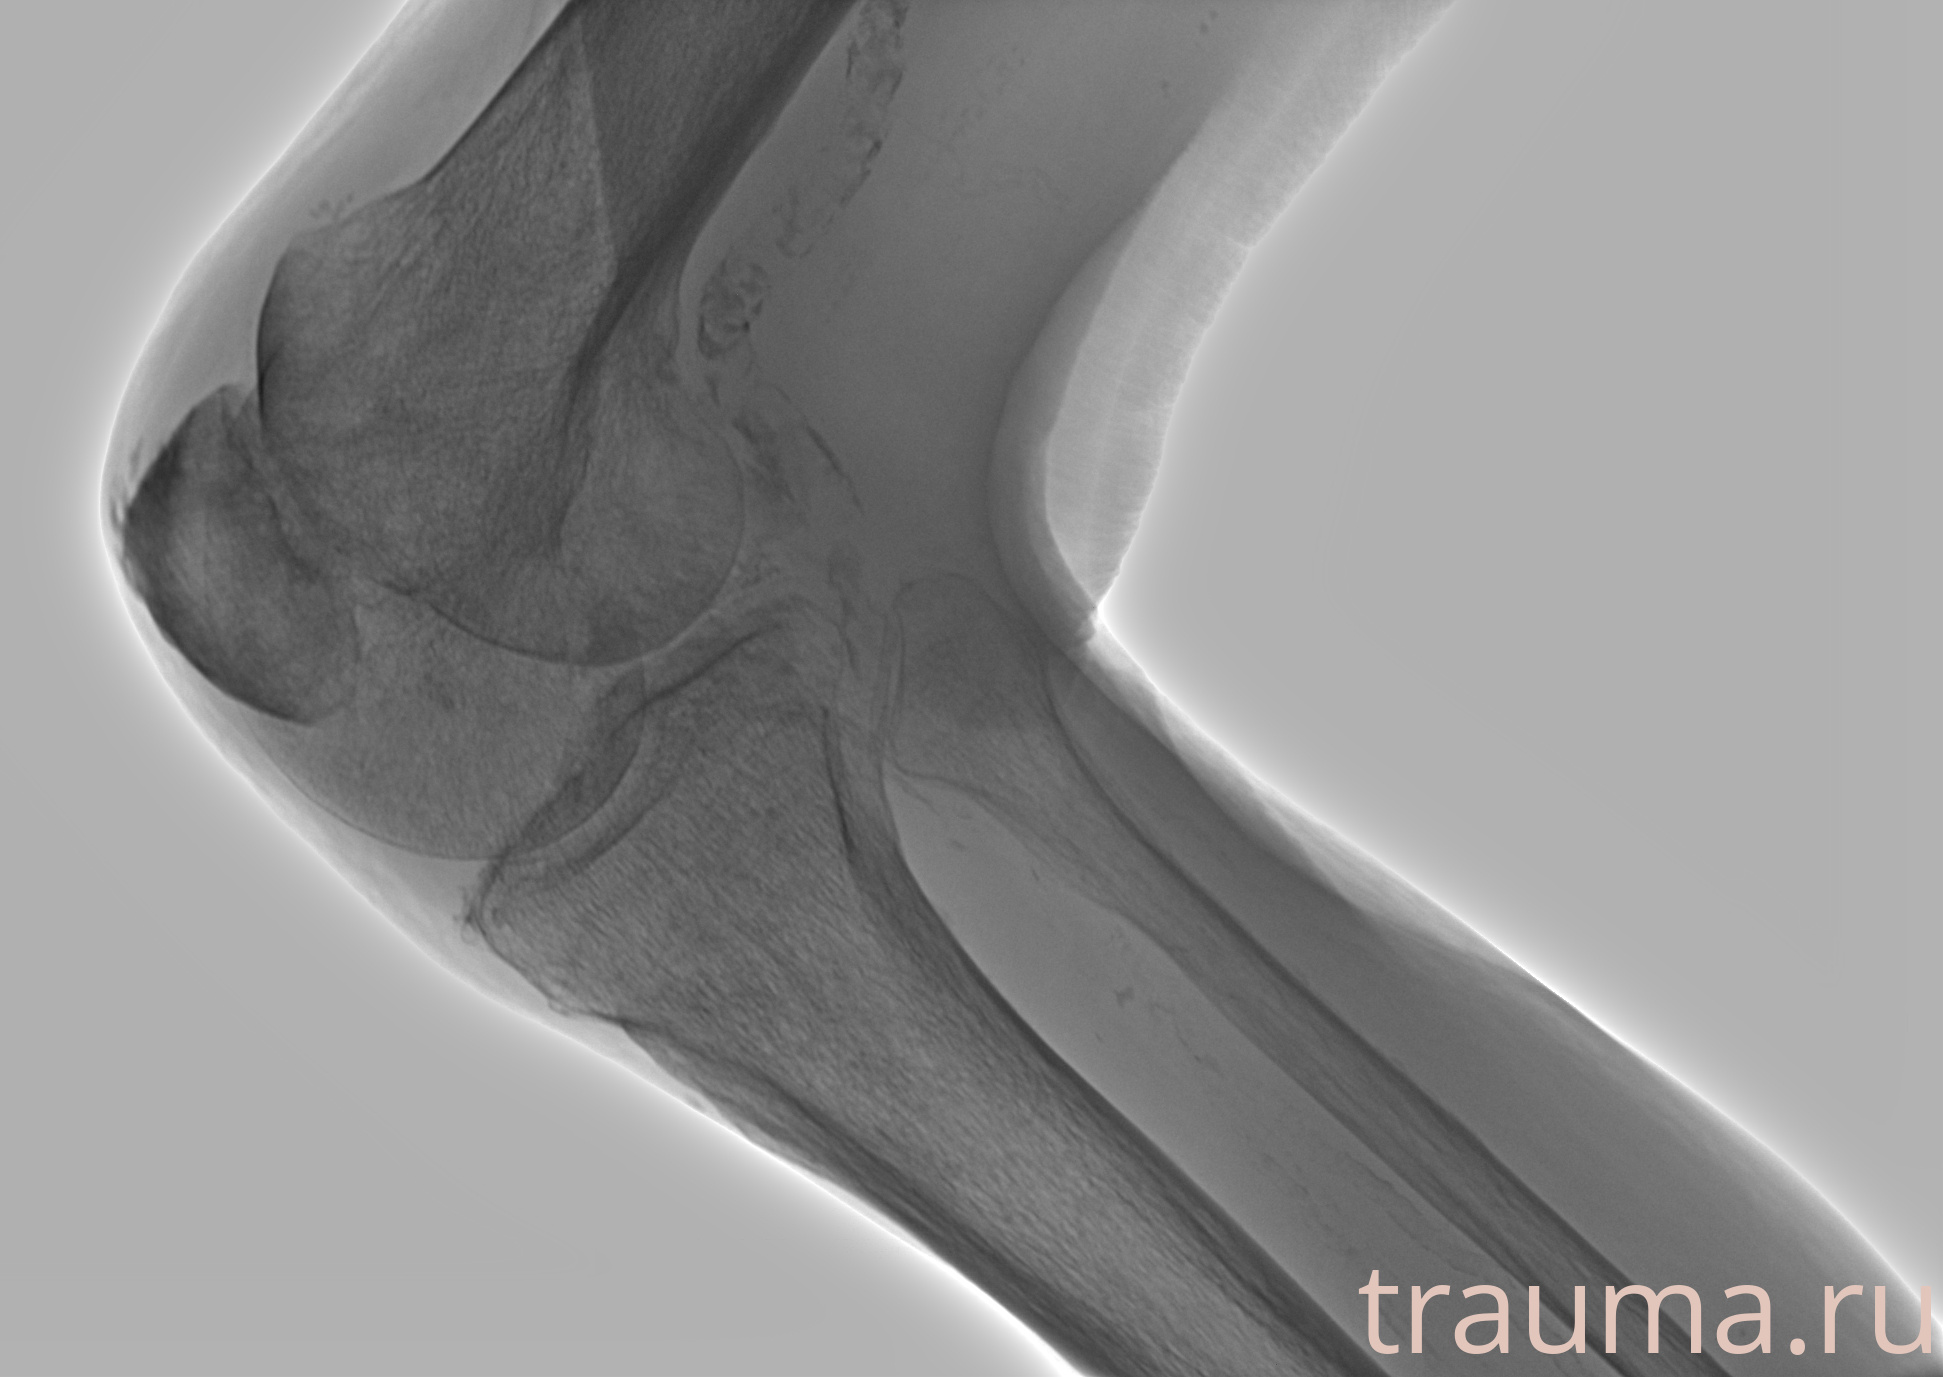

Рентгенограммы

Рентген на дому: по вашему адресу приезжает врач-рентгенолог, травматолог-ортопед с мобильным рентгеновским аппаратом, проводит диагностику травмы или заболевания, делает необходимые рентгенограммы, дает рекомендации по дальнейшему лечению. Получить качественные снимки в домашних условиях возможно благодаря уникальной методике, разработанной МосРентген Центром для института  Склифосовского